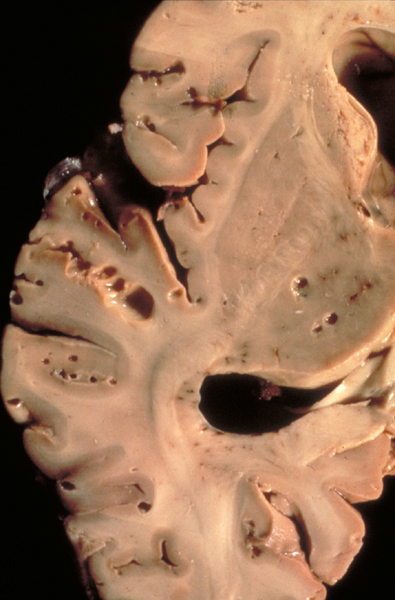

Cryptococcus is an oval yeast about the size of a red cell, surrounded by a gelatinous capsule. There are several species of cryptococcus. The most common, cryptococcus neoformans, causes 95% of infections. It is a worldwide fungus, present in bird droppings, vegetables, and soil. It may affect healthy individuals but is particularly common in immunodeficient patients, especially patients with HIV/AIDS. It is most often community-acquired. The portal of entry is the respiratory tract but pulmonary infection may be asymptomatic or minimally symptomatic. Cryptococcus spreads to the brain from the lungs and often causes meningitis without involving other organs. In the CNS, cryptococcus grows extensively in the subarachnoid space and perivascular spaces, which become cystically distended to the point that brain sections look like Swiss cheese. In immunosuppressed individuals, inflammation is absent or mild. In immunocompetent hosts, cryptococcus elicits a cell-mediated immune reaction with lymphocytes and epithelioid cell granulomas. Rarely cryptococcus may cause mass lesions (cryptococcomas). Cryptococcus meningitis has an insidious onset and may go on from weeks to years. It can cause hydrocephalus, dementia, cranial neuropathies and focal neurological deficits. The CSF in cryptococcosis shows mononuclear pleocytosis, elevated protein, and low glucose, similar to tuberculous meningitis. Yeasts can be identified by microscopy of the CSF and their antigens can be detected by latex agglutination.